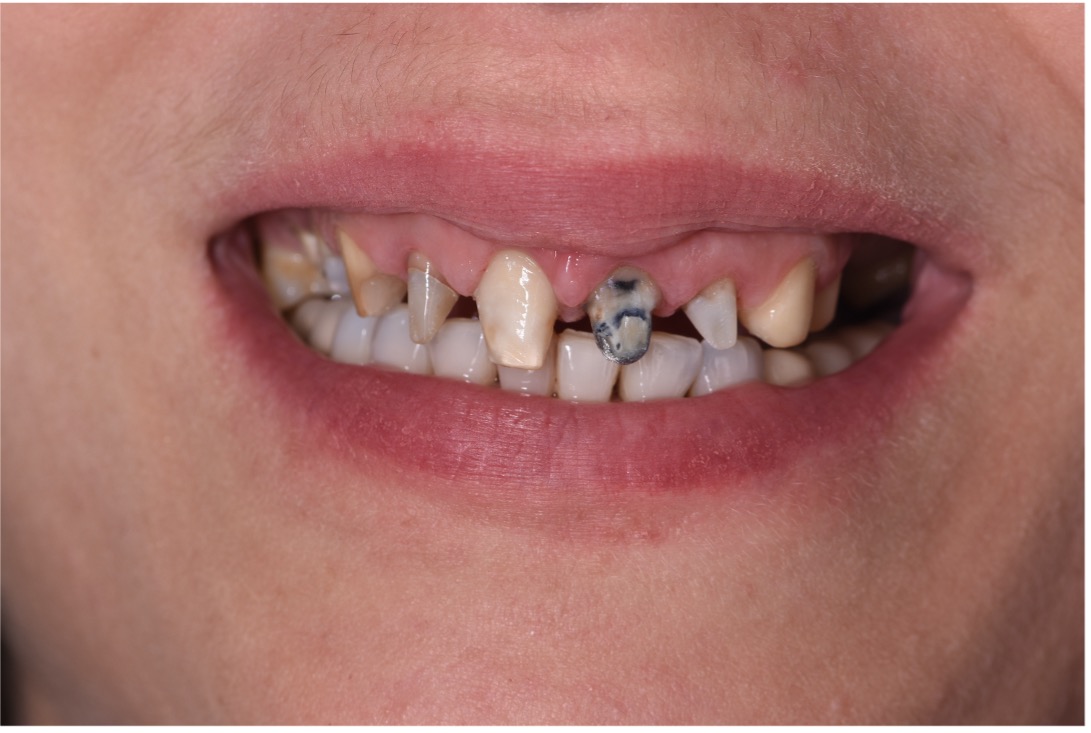

• Chief Complaint: Gummy Smile and Old Crowns

• Initial Diagnosis: Excessive Gummy Smile and Discolored old crowns

• Treatment Goals: Digital Guided Crown Lengthening and Full Upper Ceramic Rehabilitation

The primary objective of this treatment was to improve the patient's smile by addressing a pronounced gummy smile and restoring the correct proportions of the teeth by removing old crowns and replace them with new ceramic crown that are made based on a digital smile design. The treatment aimed to create a more balanced, natural-looking, and harmonious appearance that aligned with the patient’s facial features. This goal was achieved through a multidisciplinary strategy combining digital smile design, periodontal correction, and prosthodontic restoration. Leveraging AI-driven designing and treatment planning tools and advanced digital and clinical techniques, the approach focused on enhancing esthetics and function while maintaining a conservative and patient-focused methodology.